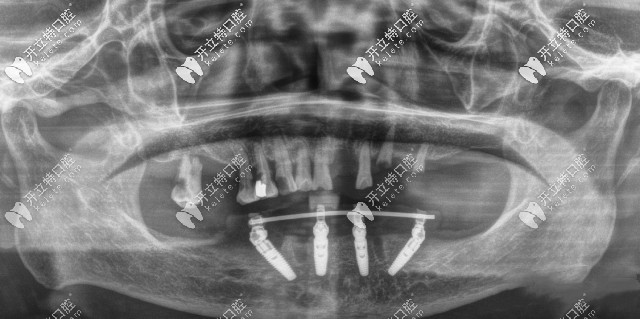

廣州廣大口腔ALLON4半口種植牙CT片

閑話不多說,大家還是來親眼見識一下廣州廣大口腔的種植牙怎么樣吧: